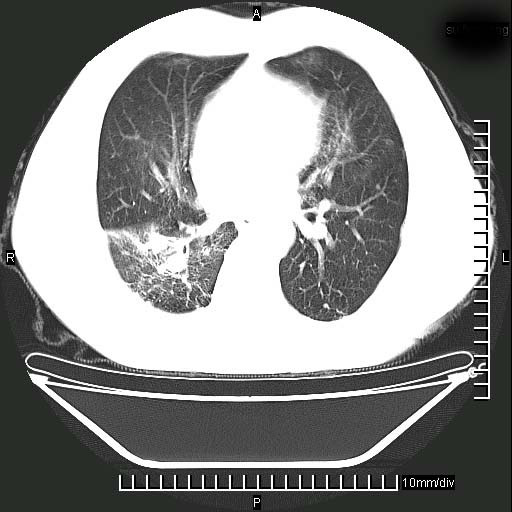

既往肺结核,近10几天,咳嗽,咳痰,右侧胸痛,疼痛较明显,右上肺斑块考虑结核灶胸膜粘连,增强,可惜动脉期没有定好,未见强化,可延迟4分后又见较明显强化,中心见低密度影,如果说结核是边缘强化,可这个灶强化的面积挺大的,让人很挠头。

动脉期